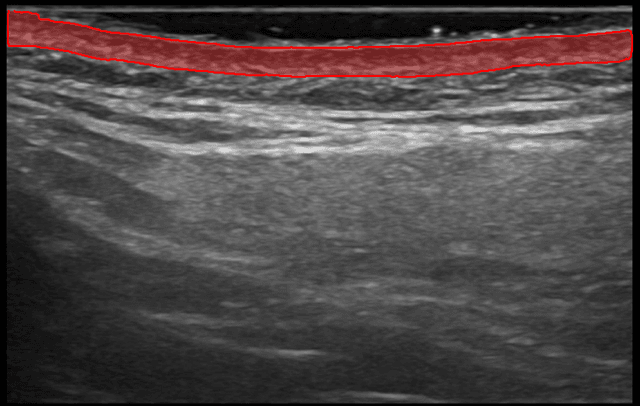

Nuestra IA segmenta instantáneamente tu capa dérmica. Obtén mediciones precisas de el grosor y el área de la dermis.

Sigue mejoras medibles a lo largo de las sesiones de tratamiento. Visualiza cambios en la calidad de la dermis con comparaciones precisas de antes y después.